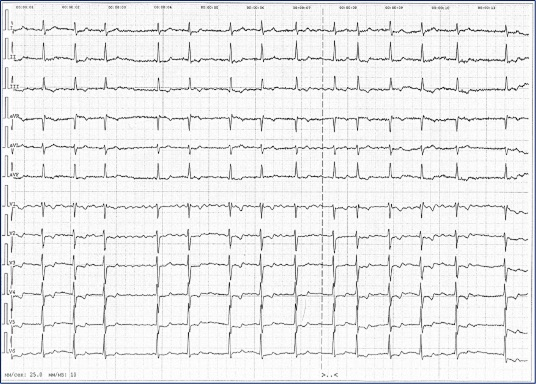

Электрокардиграфия

Фибрилляция предсердий с частотой 115–52 в минуту.

П/вертикальная ЭОС.  Неполная блокада правой ножки п. Гиса.

Изменения в миокарде, более выраженные в передней, верхушечной обл. левого желудочка.